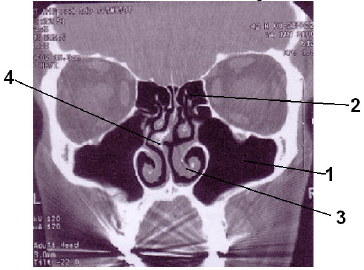

Assinale a alternativa que apresenta, na seqüência correta, as estruturas anatômicas identificadas na imagem abaixo.

Assinale a alternativa que representa, em ordem crescente, as estruturas assinaladas na imagem tomográfica anteriormente apresentada.